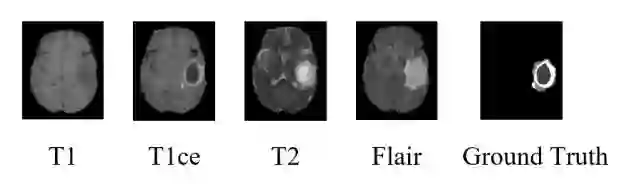

Automatic segmentation of glioma and its subregions is of great significance for diagnosis, treatment and monitoring of disease. In this paper, an augmentation method, called TensorMixup, was proposed and applied to the three dimensional U-Net architecture for brain tumor segmentation. The main ideas included that first, two image patches with size of 128 in three dimensions were selected according to glioma information of ground truth labels from the magnetic resonance imaging data of any two patients with the same modality. Next, a tensor in which all elements were independently sampled from Beta distribution was used to mix the image patches. Then the tensor was mapped to a matrix which was used to mix the one-hot encoded labels of the above image patches. Therefore, a new image and its one-hot encoded label were synthesized. Finally, the new data was used to train the model which could be used to segment glioma. The experimental results show that the mean accuracy of Dice scores are 91.32%, 85.67%, and 82.20% respectively on the whole tumor, tumor core, and enhancing tumor segmentation, which proves that the proposed TensorMixup is feasible and effective for brain tumor segmentation.